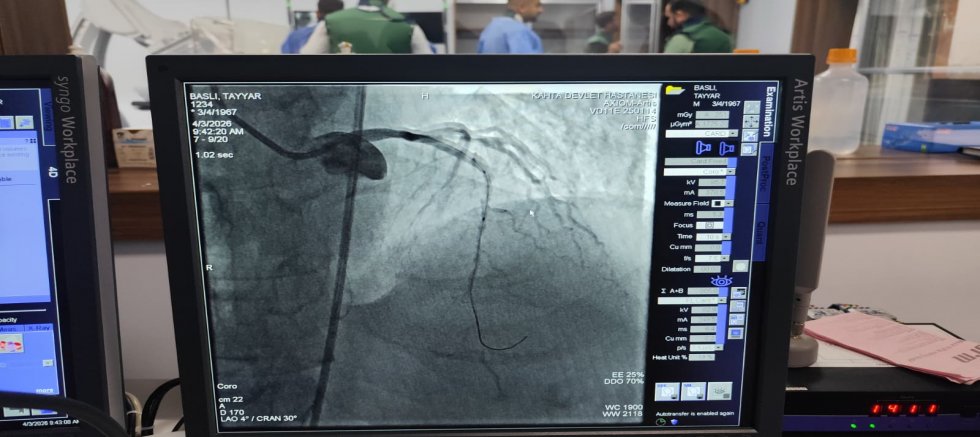

KÂHTA’DA AÇILAN ANJİYO ÜNİTESİNDE İLK HASTA BAŞARIYLA TEDAVİ EDİLDİ